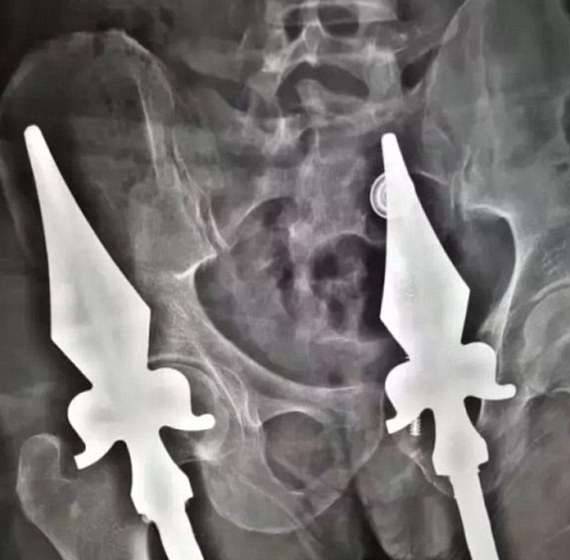

▼因为这名男子坠下时呈坐姿,铁围栏的两条钢筋尖端完全没入他的体内,无法立即取出。

▼男子随后被送到医院,医生通过手术取出了插在他体内的护栏,现在他已经脱离危险。